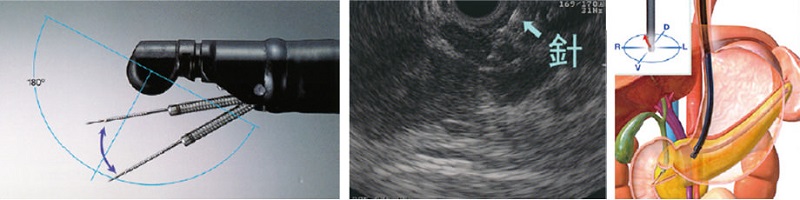

1.超音波内視鏡

内視鏡に超音波検査のプローブ(探触子)がついているものが超音波内視鏡(EUS)です。観察部位の近くから高周波数の超音波をあてられるため高い識別能力の超音波観察が可能になっています。